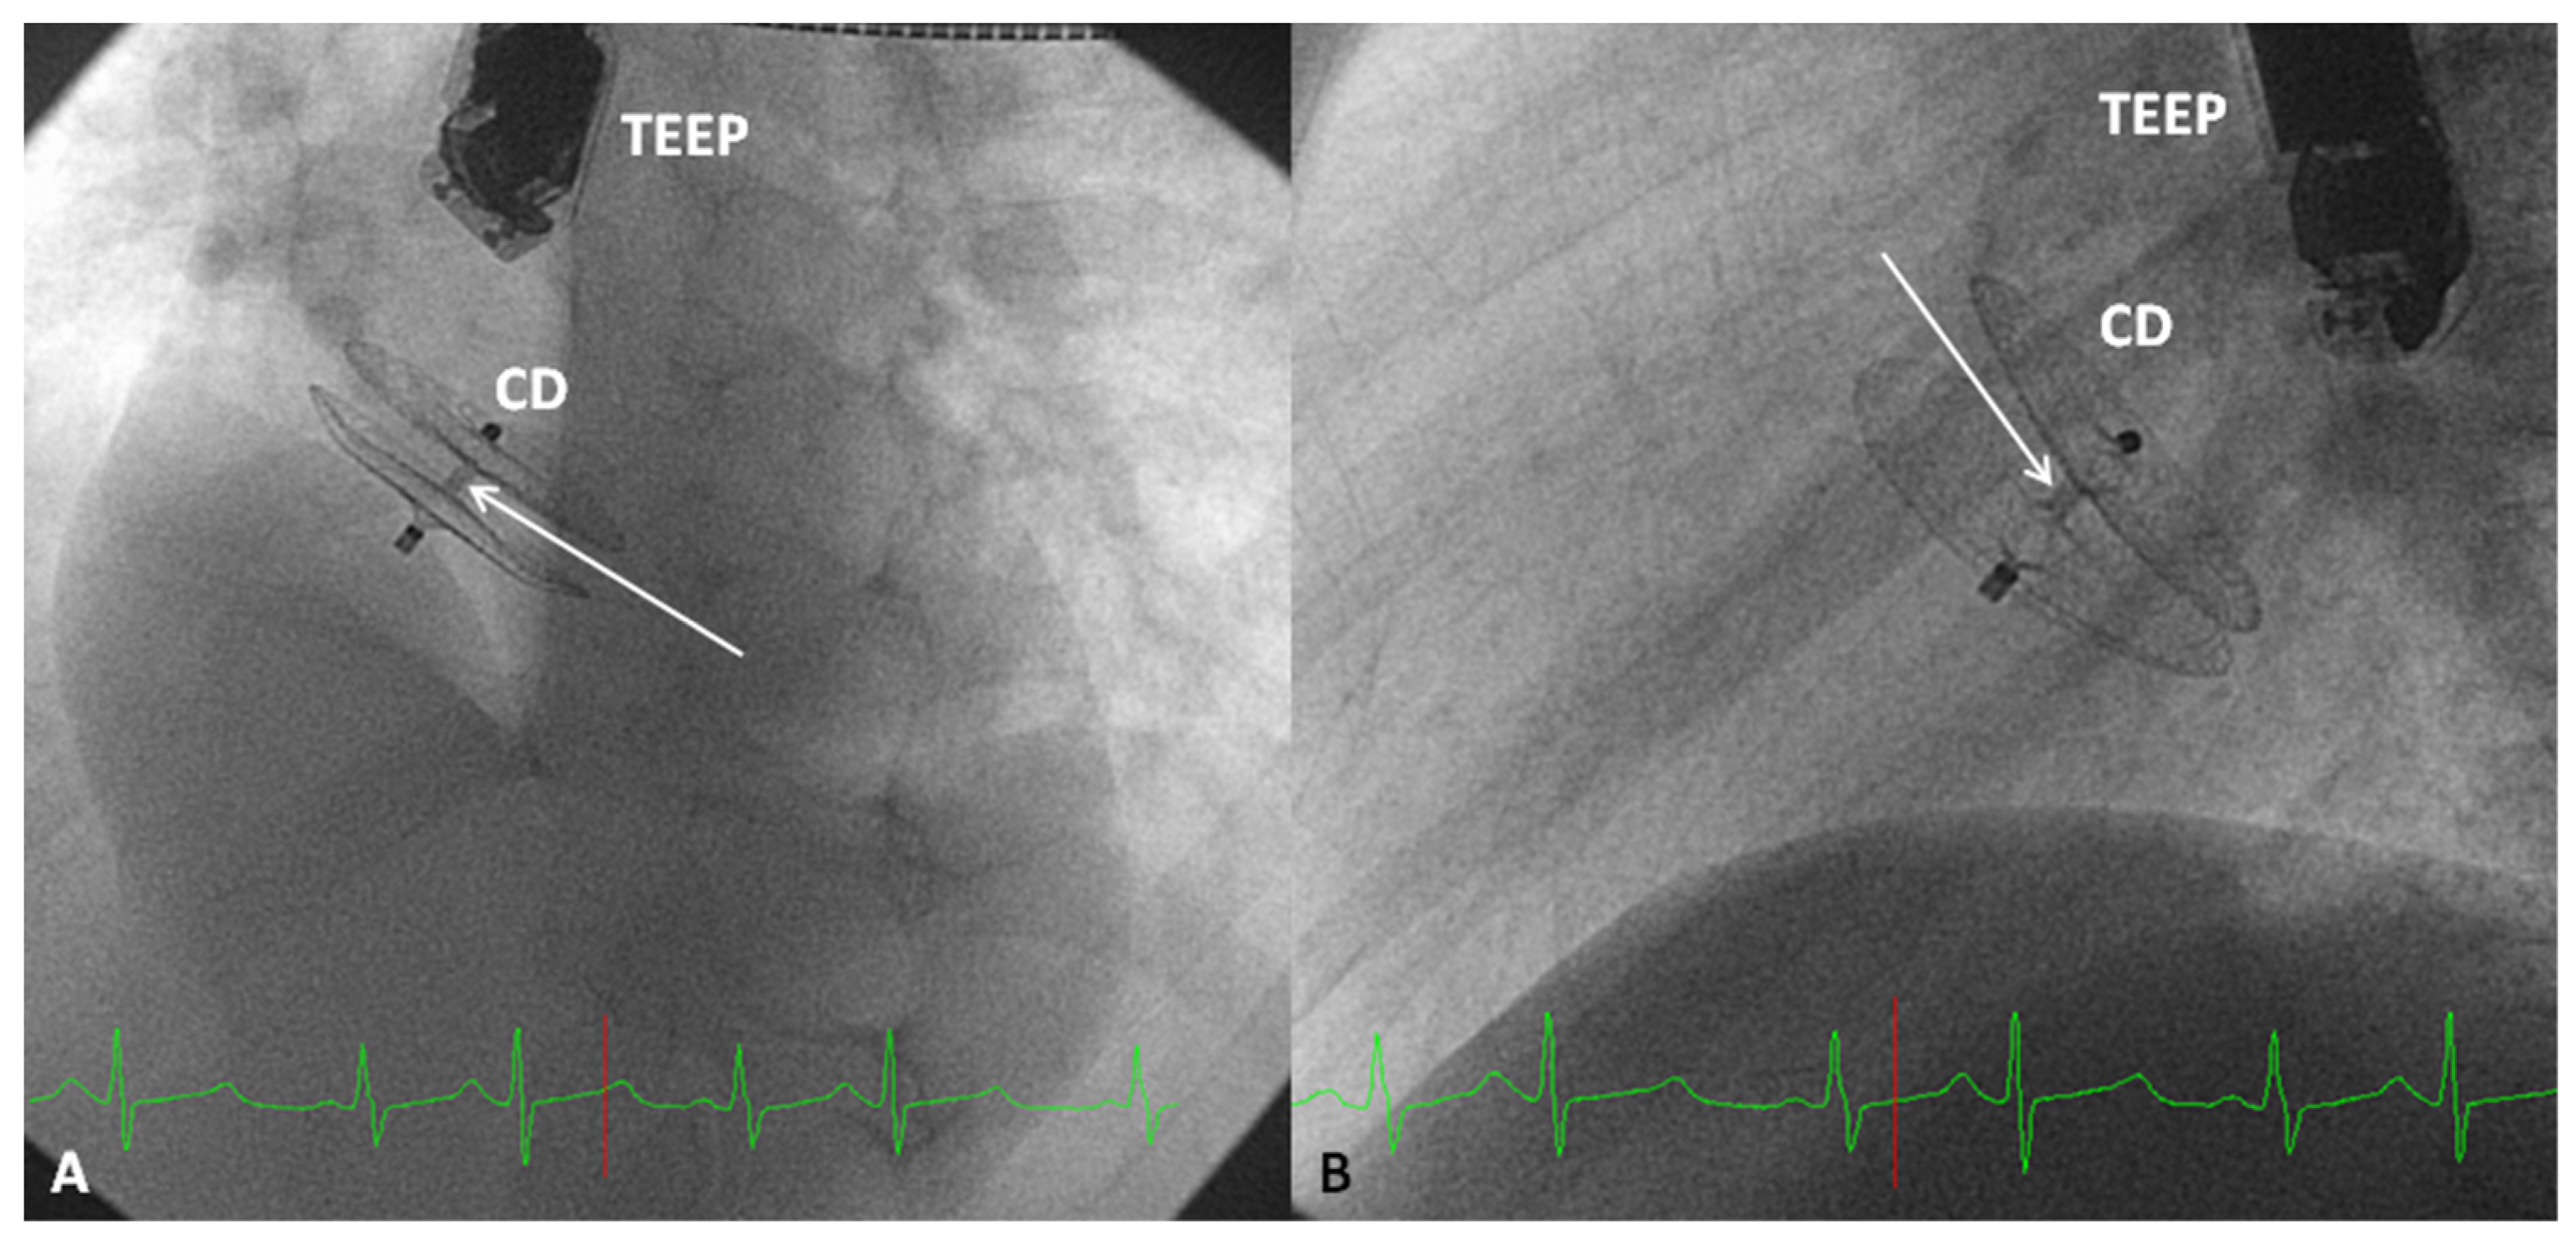

- Tsai, S.K.; Hsiung, M.C.; Wei, J.; Lee, Y.-T.; Yu, H.-P.; Ou, C.-H.; Yin, W.-H. Transesophageal echocardiography for incremental value of Amplatzer cribriform septal occluder for percutaneous transcatheter closure of complex septal defects: Case series. J. Chin. Med. Assoc. 2017, 80, 333–340. [Google Scholar] [CrossRef] [PubMed]